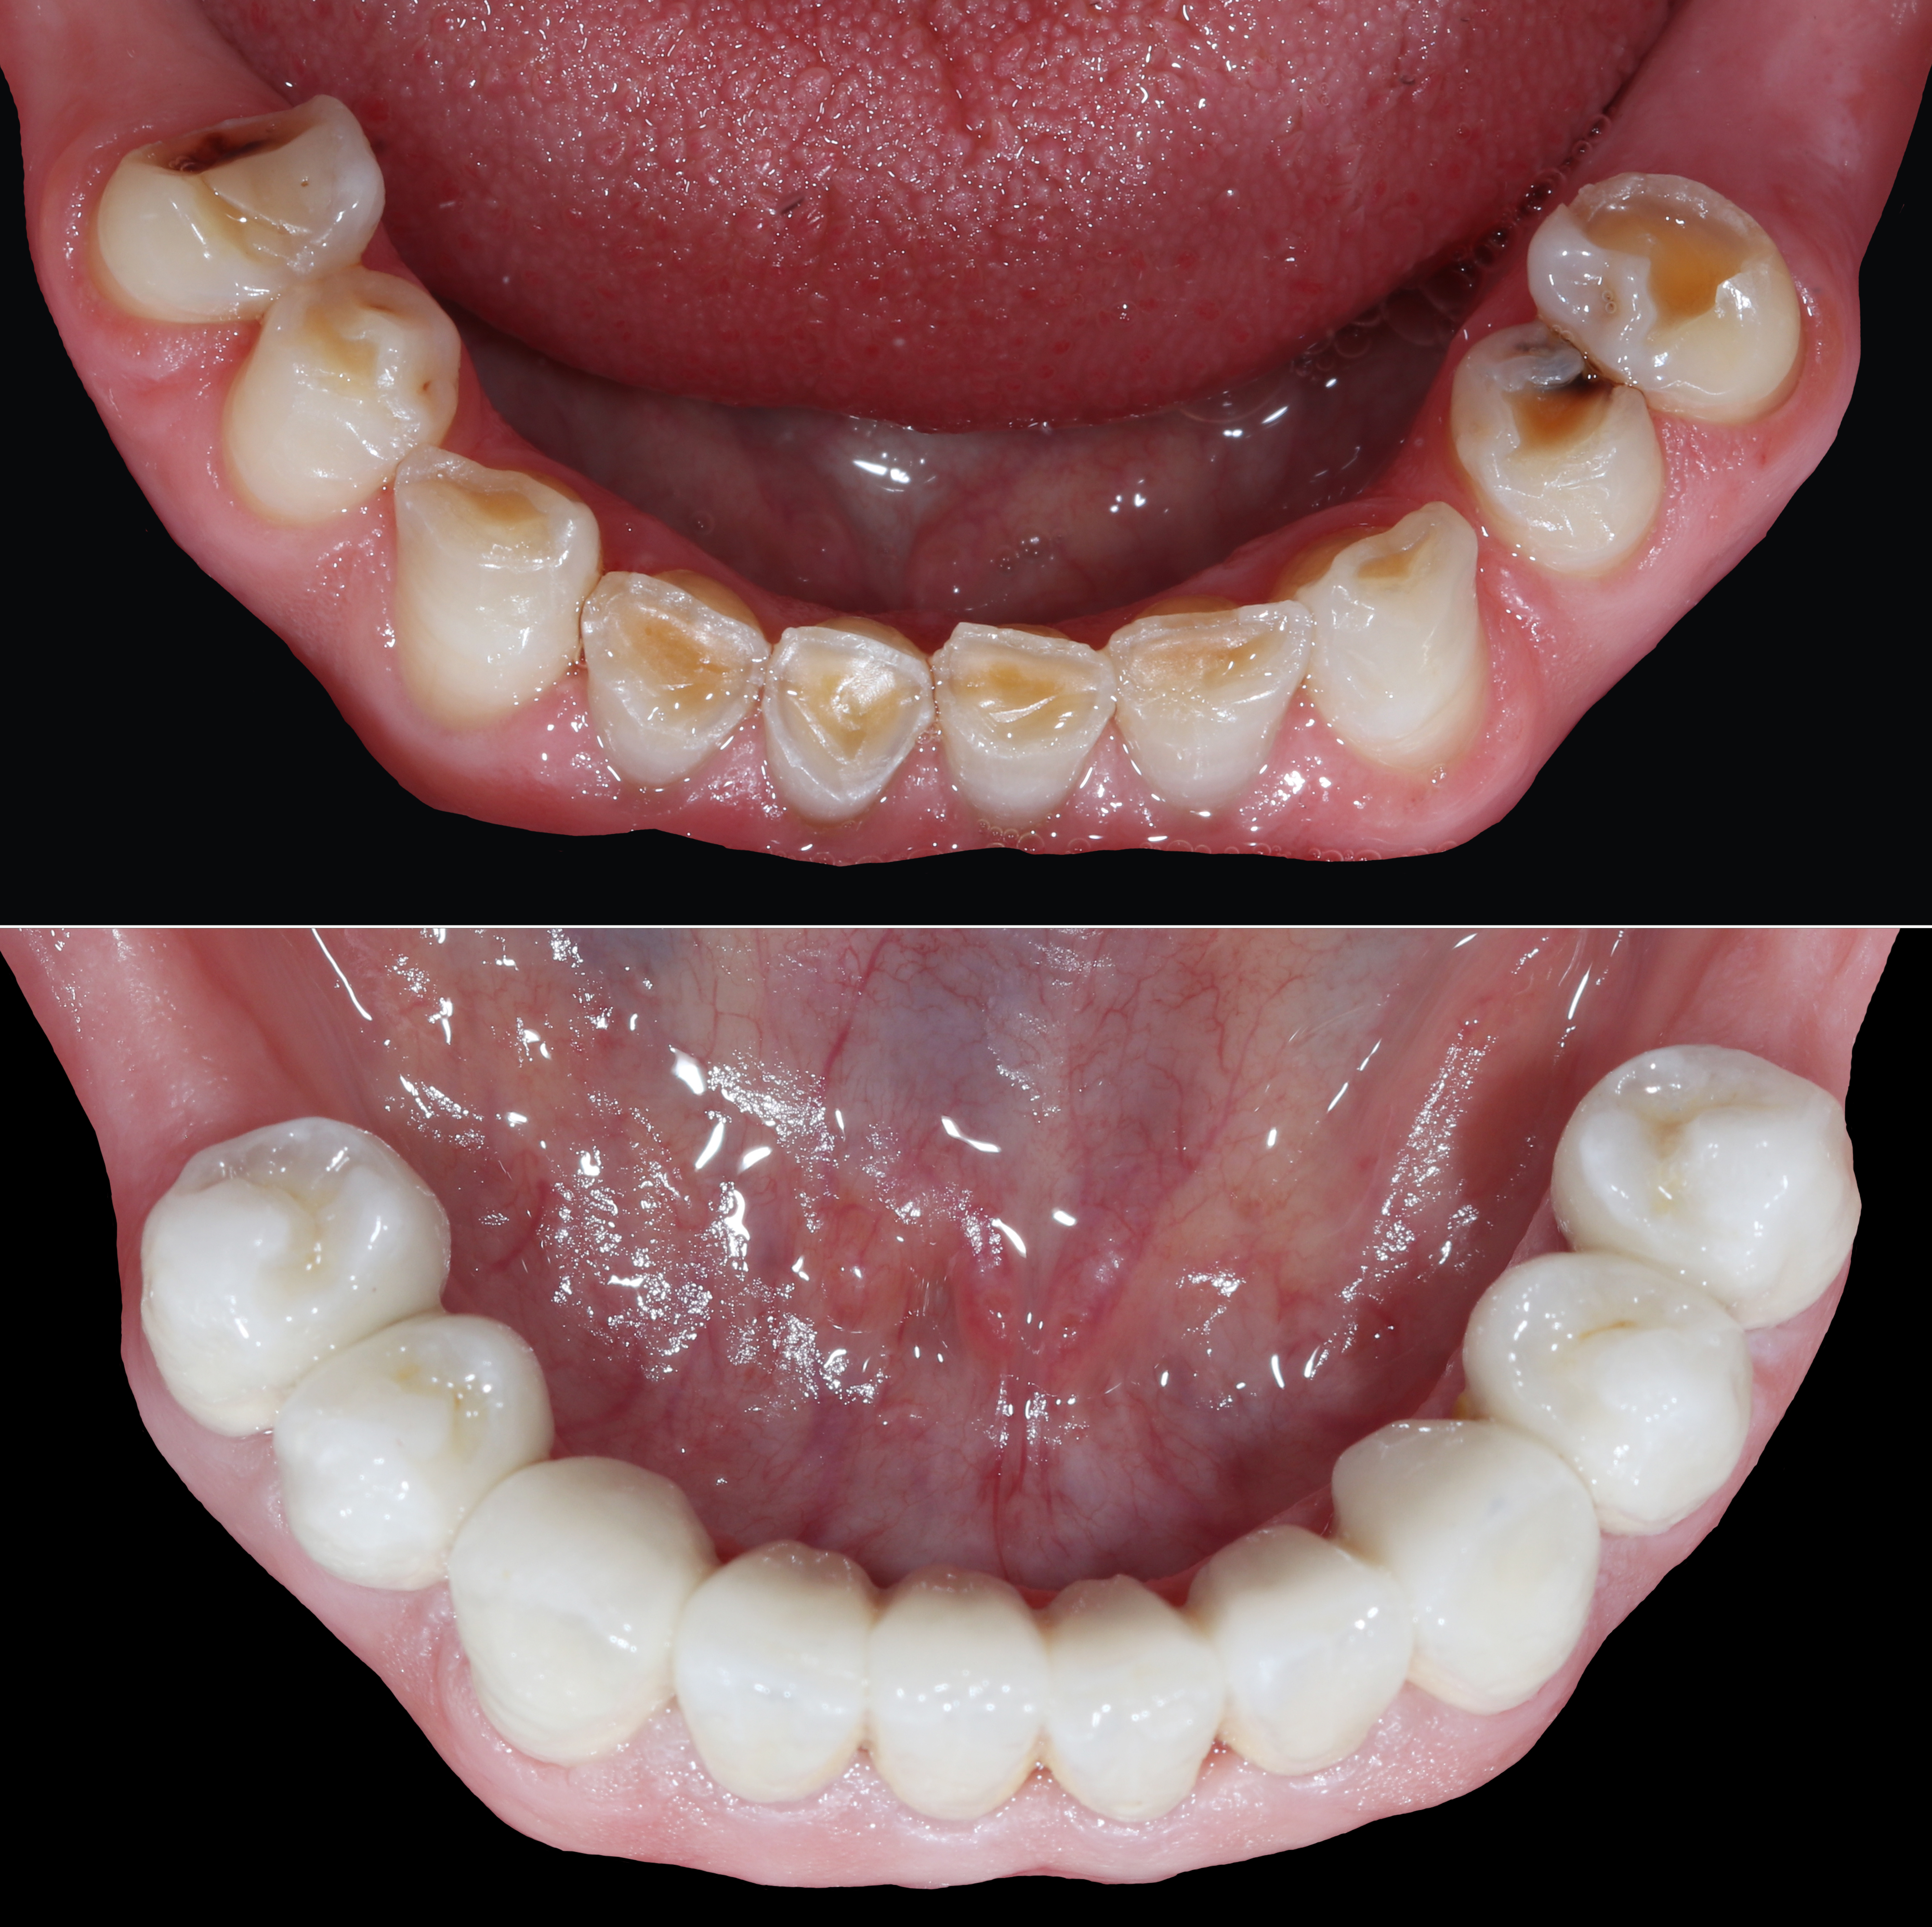

Ολική αποκατάσταση φθαρμένης και αποδιοργανωμένης οδοντοφυΐας με κεραμικές αποκαταστάσεις

Ασθενής με αποδιοργανωμένη, εκτενώς φθαρμένη οδοντοφυΐα, τερηδόνες και κατεστραμμένα δόντια στην άνω γνάθο που προκαλούσαν έντονους πόνους, προσήλθε στο Aesthetic Dental Studio στην Καλαμάτα με στόχο την αισθητική και λειτουργική αποκατάσταση του στόματός της.

Σε πρώτη φάση, αφαιρέθηκαν τα δόντια που ήταν πλήρως κατεστραμμένα, πραγματοποιήθηκαν ενδοδοντικές θεραπείες στα δόντια που μπορούσαν να αποκατασταθούν και έγιναν εμφράξεις σε δόντια με απλή τερηδόνα. Έτσι, το στόμα σταθεροποιήθηκε και ήταν πλέον έτοιμο για την δεύτερη φάση της θεραπείας, που περιελάμβανε την προσθετική αποκατάσταση των δοντιών.

Αφού όλα επιβεβαιώθηκαν, έγινε λήψη ψηφιακών αποτυπωμάτων με ενδοστοματικό σαρωτή και στην συνέχεια τοποθετήθηκαν ακίνητες κεραμικές αποκαταστάσεις ολικής επικάλυψης (στεφάνες και γέφυρες).

Το τελικό αποτέλεσμα ήταν αισθητικά άρτιο και λειτουργικά σταθερό, προσαρμοσμένο στις ανάγκες της ασθενούς.